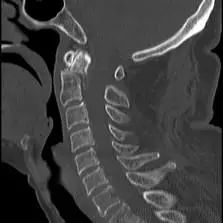

经过全程监护和系统治疗,患者术后恢复良好,骨折解剖复位,复查X线及CT显示固定位置佳,术后3天下地行走,术后4天即出院回家休养。

该手术为我市首例完成C1、2椎弓根钉棒系统固定手术,填补了枣庄在上颈椎外伤手术史上的空白,展现了枣庄市立医院脊柱外科不怕困难、勇于突破、积极向上的精神面貌,也是王存平主任技术高超、胆大心细的具体体现。